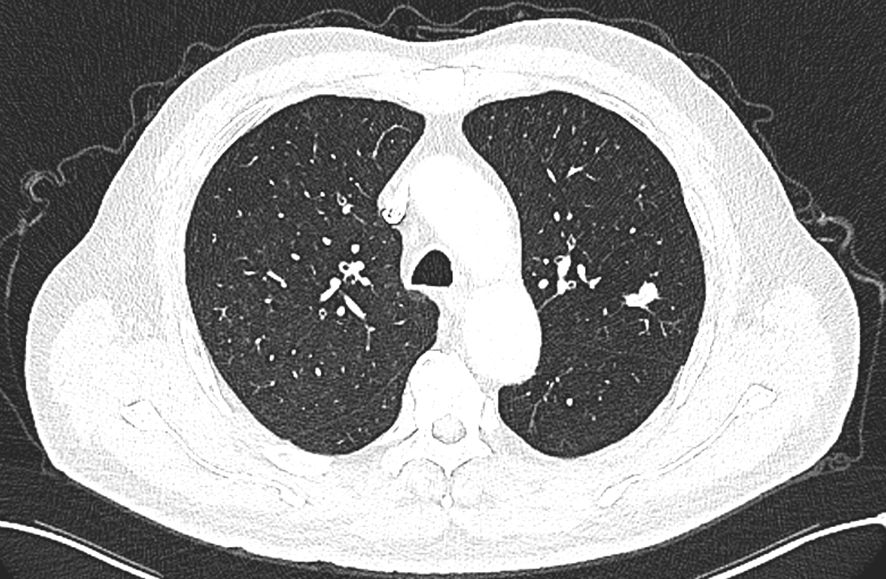

The patient is a 58-year-old male who was admitted to our hospital’s thoracic surgery department on July 26, 2024, due to a “6-month history of a left lung upper lobe nodule discovered during a routine examination.” Approximately 6 months ago, during a routine physical examination at another hospital, the patient underwent a chest CT scan which revealed multiple lung nodules, the largest of which was located in left upper lobe. He subsequently underwent regular follow-up scans. A chest CT scan performed at our hospital showed a lobulated small nodule in left upper lobe, measuring approximately 2.1 cm × 1.6 cm. Multiple small nodules in both lungs, with the largest measuring approximately 0.5 cm, recommended for follow-up examination. No significant enlargement of lymph nodes in mediastinum was observed (Figure 3). The patient reported no symptoms. He has a 10-year history of hypertension and a 30-year history of heavy smoking and drinking. There were no significant findings during physical examination upon admission. Blood gas analysis showed: pH 7.48, blood glucose 10.70 mmol/L, K+ 2.80 mmol/L. Routine blood, urine, and stool tests, liver and kidney function, and coagulation profile were normal. Pulmonary function testing showed FEV1 of 2.76L, indicating mild obstructive ventilatory dysfunction. The electrocardiogram showed no abnormalities. Coronary CTA revealed moderate stenosis in the proximal left anterior descending artery, mild stenosis in the proximal left circumflex artery, and mild stenosis in the right coronary artery in the mid-segment, with no significant narrowing of the other coronary arteries. Brain MRI showed signs of cerebral arteriosclerosis. Ultrasound examinations of the liver, gallbladder, pancreas, spleen, kidneys, adrenal glands, bilateral carotid arteries, bilateral lower extremity veins, and full-body bone scans were all unremarkable. The patient’s family requested surgical treatment for left upper lobe nodule regardless of whether it is benign or malignant. And refused to undergo further relevant tests to clarify the diagnosis. After excluding surgical contraindications, on July 30, the patient underwent a left upper lobectomy under general anesthesia with thoracoscopic surgery. Routine dissection of lymph nodes from groups 5, 6, 7, 9, 10 and 11. Rapid intraoperative frozen section pathology indicated invasive carcinoma and subsequent routine paraffin pathology (Figure 4) showed immunohistochemistry: CK5/6 (-), CK7 (partial +), Napsin A (-), P40 (-), P63 (-), TTF-1 (partial +), CD56 (partial +), CgA (-), Syn (partial +), SSTR2 (-), SMARCA4 (+), CK (+), Ki67 (+, approximately 80%). Based on the immunohistochemistry results, the diagnosis was consistent with a composite small cell carcinoma (neuroendocrine carcinoma + large cell carcinoma). The tumor measured approximately 2.5 × 2 × 2 cm and did not invade pleura. Metastatic cancer was found in the 6th group lymph nodes (2/2) and the 11th group lymph nodes (1/7), no metastatic cancer was observed in other lymph node groups. Based on pathology report, the clinical stage was T1cN2bM0, which corresponds to stage IIIA. Postoperatively, no special treatment was given. After discharge, the patient reported no significant discomfort. Chest CT re-examination at 1st and 10th month post-surgery showed no significant abnormalities (Table 1).

Figure 3

CT scan of a thorax displaying lung fields with a central heart silhouette. The scan reveals normal lung textures and structures, with no apparent abnormalities in the visible areas.

Figure 3. Lobulated nodule in the left upper lobe.